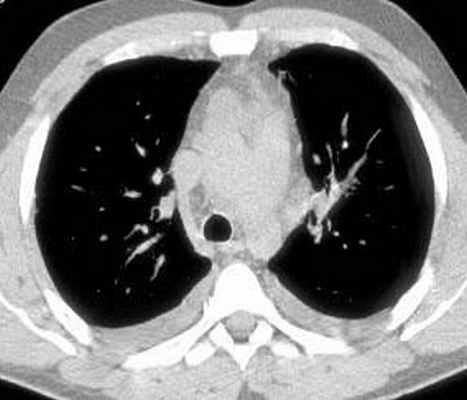

Больной С., 33 г., по профессии электромонтажник, поступил в НМХЦ им. Н.И. Пирогова 5 февраля 2007 г. с жалобами на одышку при незначительной физической нагрузке, кашель с трудноотделяемой мокротой слизистого характера, общую слабость, похудание на 10 кг, субфебрильную температуру тела. С 2000 г. у пациента диагностировали хронический ринит, синусит, полипоз носа. Для купирования затрудненного носового дыхания последние 3 года применял кортикостероидный назальный спрей. В связи с возникновением приступов удушья 2006 г. в НИИ аллергологии и иммунологии диагностирована бронхиальная астма среднетяжелого течения. Назначена терапия симбикортом с положительным эффектом. Ухудшение состояния с декабря 2006, когда появились субфебрильная температура тела, приступы затрудненного дыхания, одышка при физической нагрузке, снижение аппетита. При КТ органов грудной клетки, выполненной амбулаторно 25.01.07г.: лимфаденопатия средостения (лимфоузлы до 2-2,5 см) с образованием конгломерата размером 38 х 40 х 50 мм (рис. 1), снижение прозрачности легочной ткани по типу «матового стекла» (рис. 2а), диффузное уплотнение интерстициальной ткани (рис. 2б), двусторонний гидроторакс. Заподозрена опухоль переднего средостения в связи, с чем пациент госпитализирован для морфологической верификации диагноза.

| Рис. 1. КТ грудной клетки: а - в области вилочковой железы образование размером 38х40х50мм, б - увеличение лимфатических узлов средостения до 20-25 мм. | |